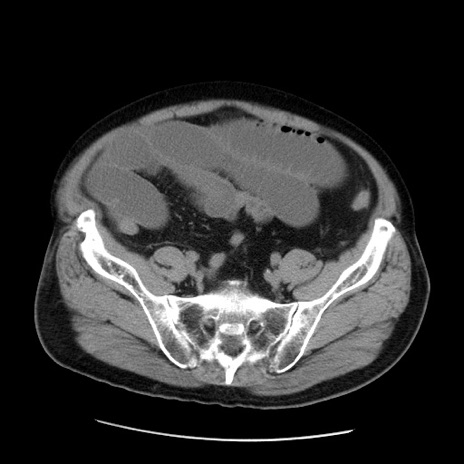

症例20(横断像)

【症例】 60歳代男性

【主訴】 腹部膨満、嘔吐

【現病歴】5日前頃より倦怠感を認め食事量減少し4日前の朝嘔吐、食事摂取困難となった。 3日前近医受診し点滴施行され整腸剤などを処方された。 当日他院を受診し、腹部膨満著明、炎症反応の上昇(CRP10.8、WBC11200)あり、紹介受診となる。

【身体所見】 意識JCS1 受け答えがはっきりしないBP 111/57mHg、 P 67bpm、、BT35.2°C、SpO2 97%(RA)、 腹部:膨隆、打診で鼓音あり、全体的に圧痛有り、腸蠕動音(-)、反跳痛ははっきりせず。

【データ】WBC 11400、CRP 14.20